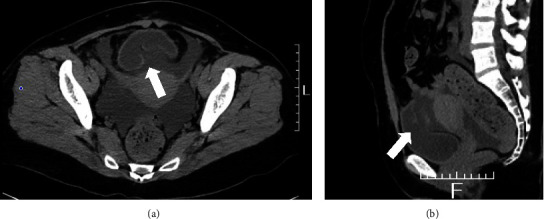

Catatonia is a psychiatric emergency in schizophrenia that often leads to excessive activation of the sympathetic nervous system. Urinary retention in catatonia is often underestimated but has potentially detrimental consequences. Herein, we present the case of a woman in her 40s with schizophrenia treated for catatonia during a relapse. When treated as an inpatient, the patient suddenly complained of severe abdominal pain. Computed tomography revealed a spontaneous rupture of the posterior wall of the bladder, requiring emergency repair surgery in the urology department. The patient was readmitted to our hospital following surgery and ultimately discharged 1 month later. Bladder rupture is life-threatening, and delayed diagnosis and treatment can be fatal. This case report serves as a warning that psychiatrists should not overlook urinary retention in patients with catatonia and should consider bladder rupture in the differential diagnosis when these patients have abdominal pain.